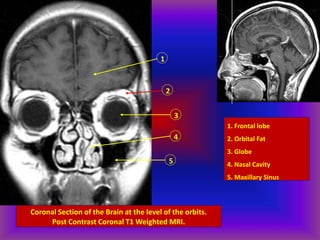

Coronal Section of the Brain at the level of the orbits.

Post Contrast Coronal T1 Weighted MRI.

1. Frontal lobe

2. Orbital Fat

3. Globe

4. Nasal Cavity

5. Maxillary Sinus